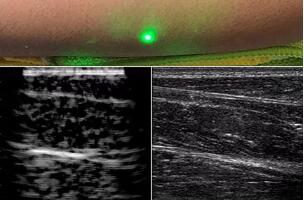

目前,研究人員已經(jīng)與健康的志愿者測試了他們的系統(tǒng):從半米遠處掃描了他們的前臂,并將這些結果與傳統(tǒng)超聲的結果進行了比較。他們能夠觀察到深達6厘米的組織,并能看到肌肉,脂肪和骨頭,并報告其結果可與標準超聲相媲美。